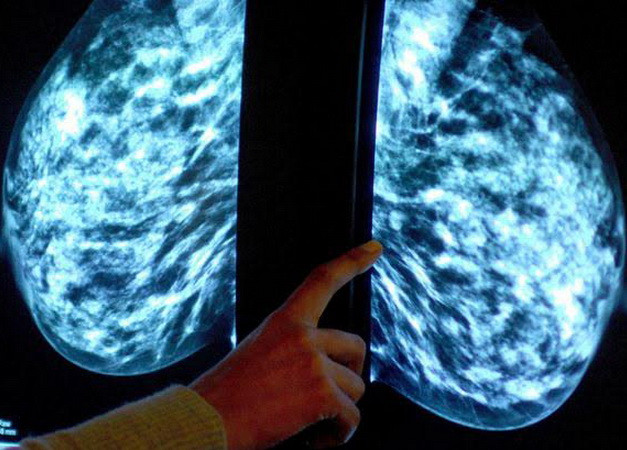

Thuốc chống ung thư vú giá rẻ mang hy vọng cho hàng triệu phụ nữ ảnh 1Chụp x-quang xác định bệnh nhân ung thư vú. (Nguồn: Mirror)